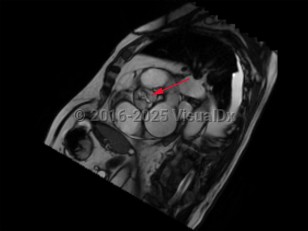

Aortic stenosis

Contributing etiologies include calcification of the aortic valve cusps (most common in the elderly population), congenital abnormalities (ie, bicuspid aortic valve), rheumatic fever, chest radiotherapy, endocarditis, and alkaptonuria. Potential complications include heart failure, cardiac arrhythmias, infectious endocarditis, pulmonary hypertension, excessive bleeding, stroke, and other embolic events.

There is no known medical therapy available to delay progression of AS. Patients should be monitored carefully with serial clinical evaluations and echocardiography in order to determine if and when aortic valve replacement is needed, which may be performed by surgical aortic valve replacement or transcatheter aortic valve replacement (TAVR), also known as transcatheter aortic valve implantation (TAVI). Prolonged or intense physical activity and competitive sports should be avoided in patients with severe AS.